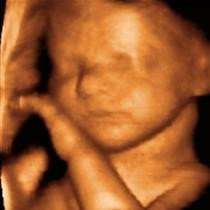

Aunque a los padres nos encante ver (cuantas más veces mejor) a nuestro bebé dentro del útero, tenemos que entender que las ecografías no son un video, sino un método diagnóstico.

Médicos de la Canadian Medical Association están advirtiendo sobre posibles riesgos relacionados a la sobreexposición de las frecuencias de ultrasonido que se emiten al realizar una ecografía.

Según un estudio, un exceso de sesiones podría causar retraso del habla, daño celular y bajo peso al nacer.